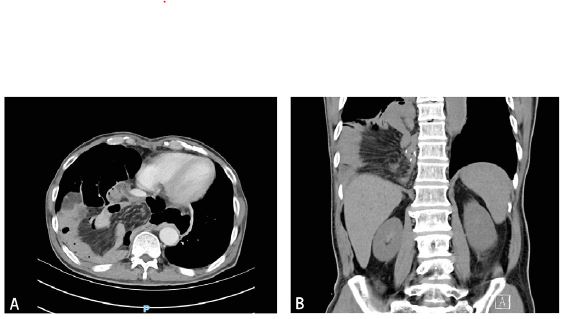

Subsequently, we performed an emergency exploratory laparotomy. During surgery, the small intestine was observed herniating into the thoracic cavity through the hiatal hernia (Figure 3A), with no evidence of local recurrence, peritoneal disease, or liver metastasis. The small intestine was repositioned, showing no evident signs of ischemic necrosis, and a defect at the diaphragmatic angle was observed (Figure 3B). Notably, upon extending through the hiatus into the thoracic cavity, no pleura was observed (Figure 3C). We decided to perform hernia repair surgery and secured the intestine to the hiatus (Figure 3D). A drainage tube was placed behind the esophagojejunostomy site during the surgery. The nasogastric tube was removed on the same day postoperatively, and the patient began passing gas and consuming liquids two days later. The patient was discharged cured five days after surgery. At a three-month follow-up, the patient reported no abdominal discomfort.

Figure 3: Laparoscopic repositioning of the small intestine and hernia defect repair.

A. Non-traumatic laparoscopic clamp repositioning;

B. Muscular defect in the diaphragmatic crura;

C. Pleural defect;

D. Hernia defect repair with 3-0 barbed suture and 3-0 non-absorbable suture.